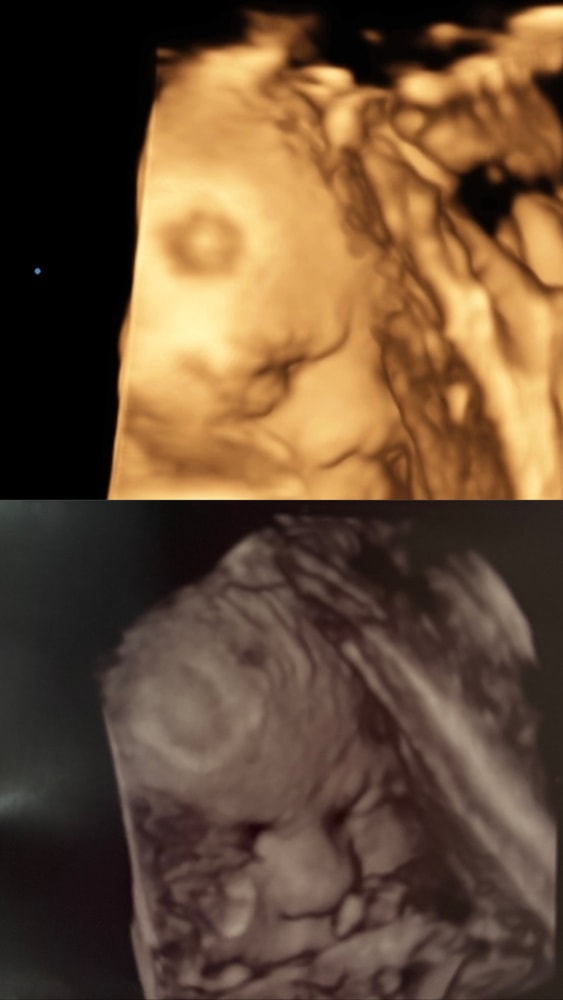

Узи 4d

УЗИ, КТГ, доплерДве фотографии были сделаны в разные сроки. В 35 недель и 39. Волнует эта точка в одном и том же месте, что это может быть??? Все хорошо по узи, никто ничего плохого не говорил никогда.

Это, вероятно, место, в которое ребенок головой упирается. Не пытайтесь ничего найти на фотке 4д, это бессмысленно и бесполезно